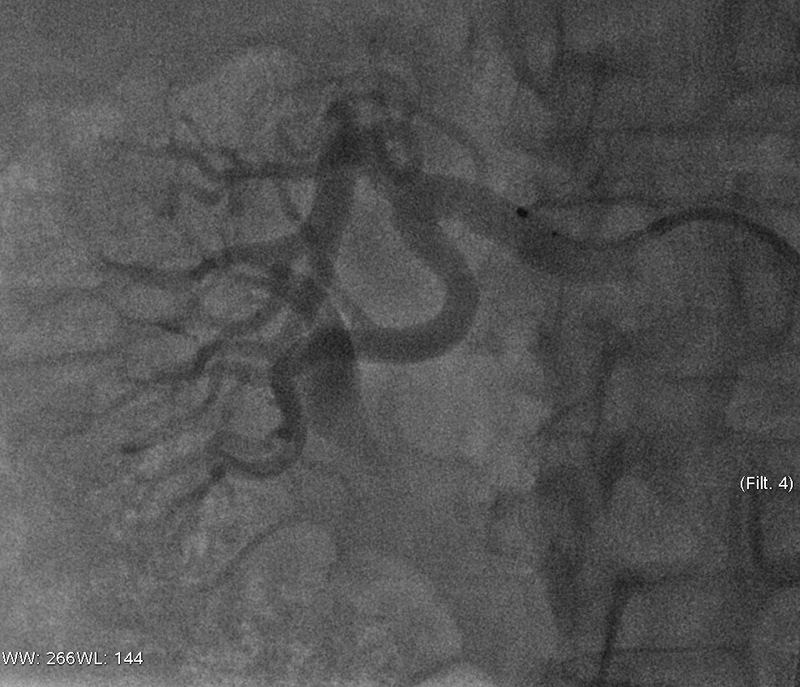

Symplicity HTN-2 var en randomisert internasjonal studie hvor målet var å se på effekten av renal denervering ved behandlingsresistent hypertensjon (14). De inkluderte pasientene (18 – 85 år) hadde et kontorblodtrykk på over 160 mm Hg (150 mm Hg hos pasienter med type 2-diabetes). 106 pasienter ble randomisert til enten kontrollgruppe (n = 54) eller intervensjonsgruppe (n = 52). Kateterbasert nyrearterieablasjon ble hos intervensjonsgruppen utført med bruk av Symplicity Catheter System, mens kontrollgruppen fortsatte sitt medikamentregime.

Intervensjonsgruppen hadde et gjennomsnittlig blodtrykk ved start på 178/97 mm Hg, kontrollgruppens startblodtrykk var 178/98 mm Hg. Medikamentbruken var henholdsvis 5,2 og 5,3 antihypertensive midler. Ved seksmånederskontrollen var det i kontrollgruppen ingen endring fra startblodtrykket, mens intervensjonsgruppen hadde en gjennomsnittlig reduksjon på 32/12 mm Hg (fig 4) (14). Nyrefunksjonen var uendret i begge gruppene, også hos dem som hadde eGFR på 45 – 60 ml/min/1,73 m² (14).